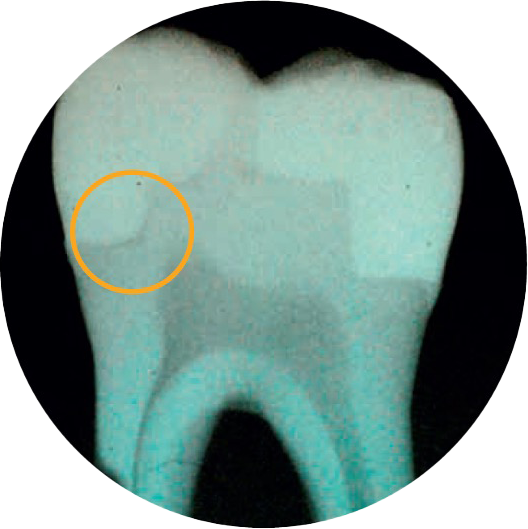

Uncertain of gap formation?

2 out of 3 dentists indicate cavity adaptation is the most important attribute for a successful restoration.4

You'll love SDR flow+ Bulk Fill Flowable!

SDR flow+ material is a one-of-a-kind breakthrough in dentistry—a bulk fill flowable that combines exclusive self-leveling properties and category-best shrinkage stress—which allows for placement up to 4 mm with excellent cavity adaptation, enabling the placement of gap-free restorations.